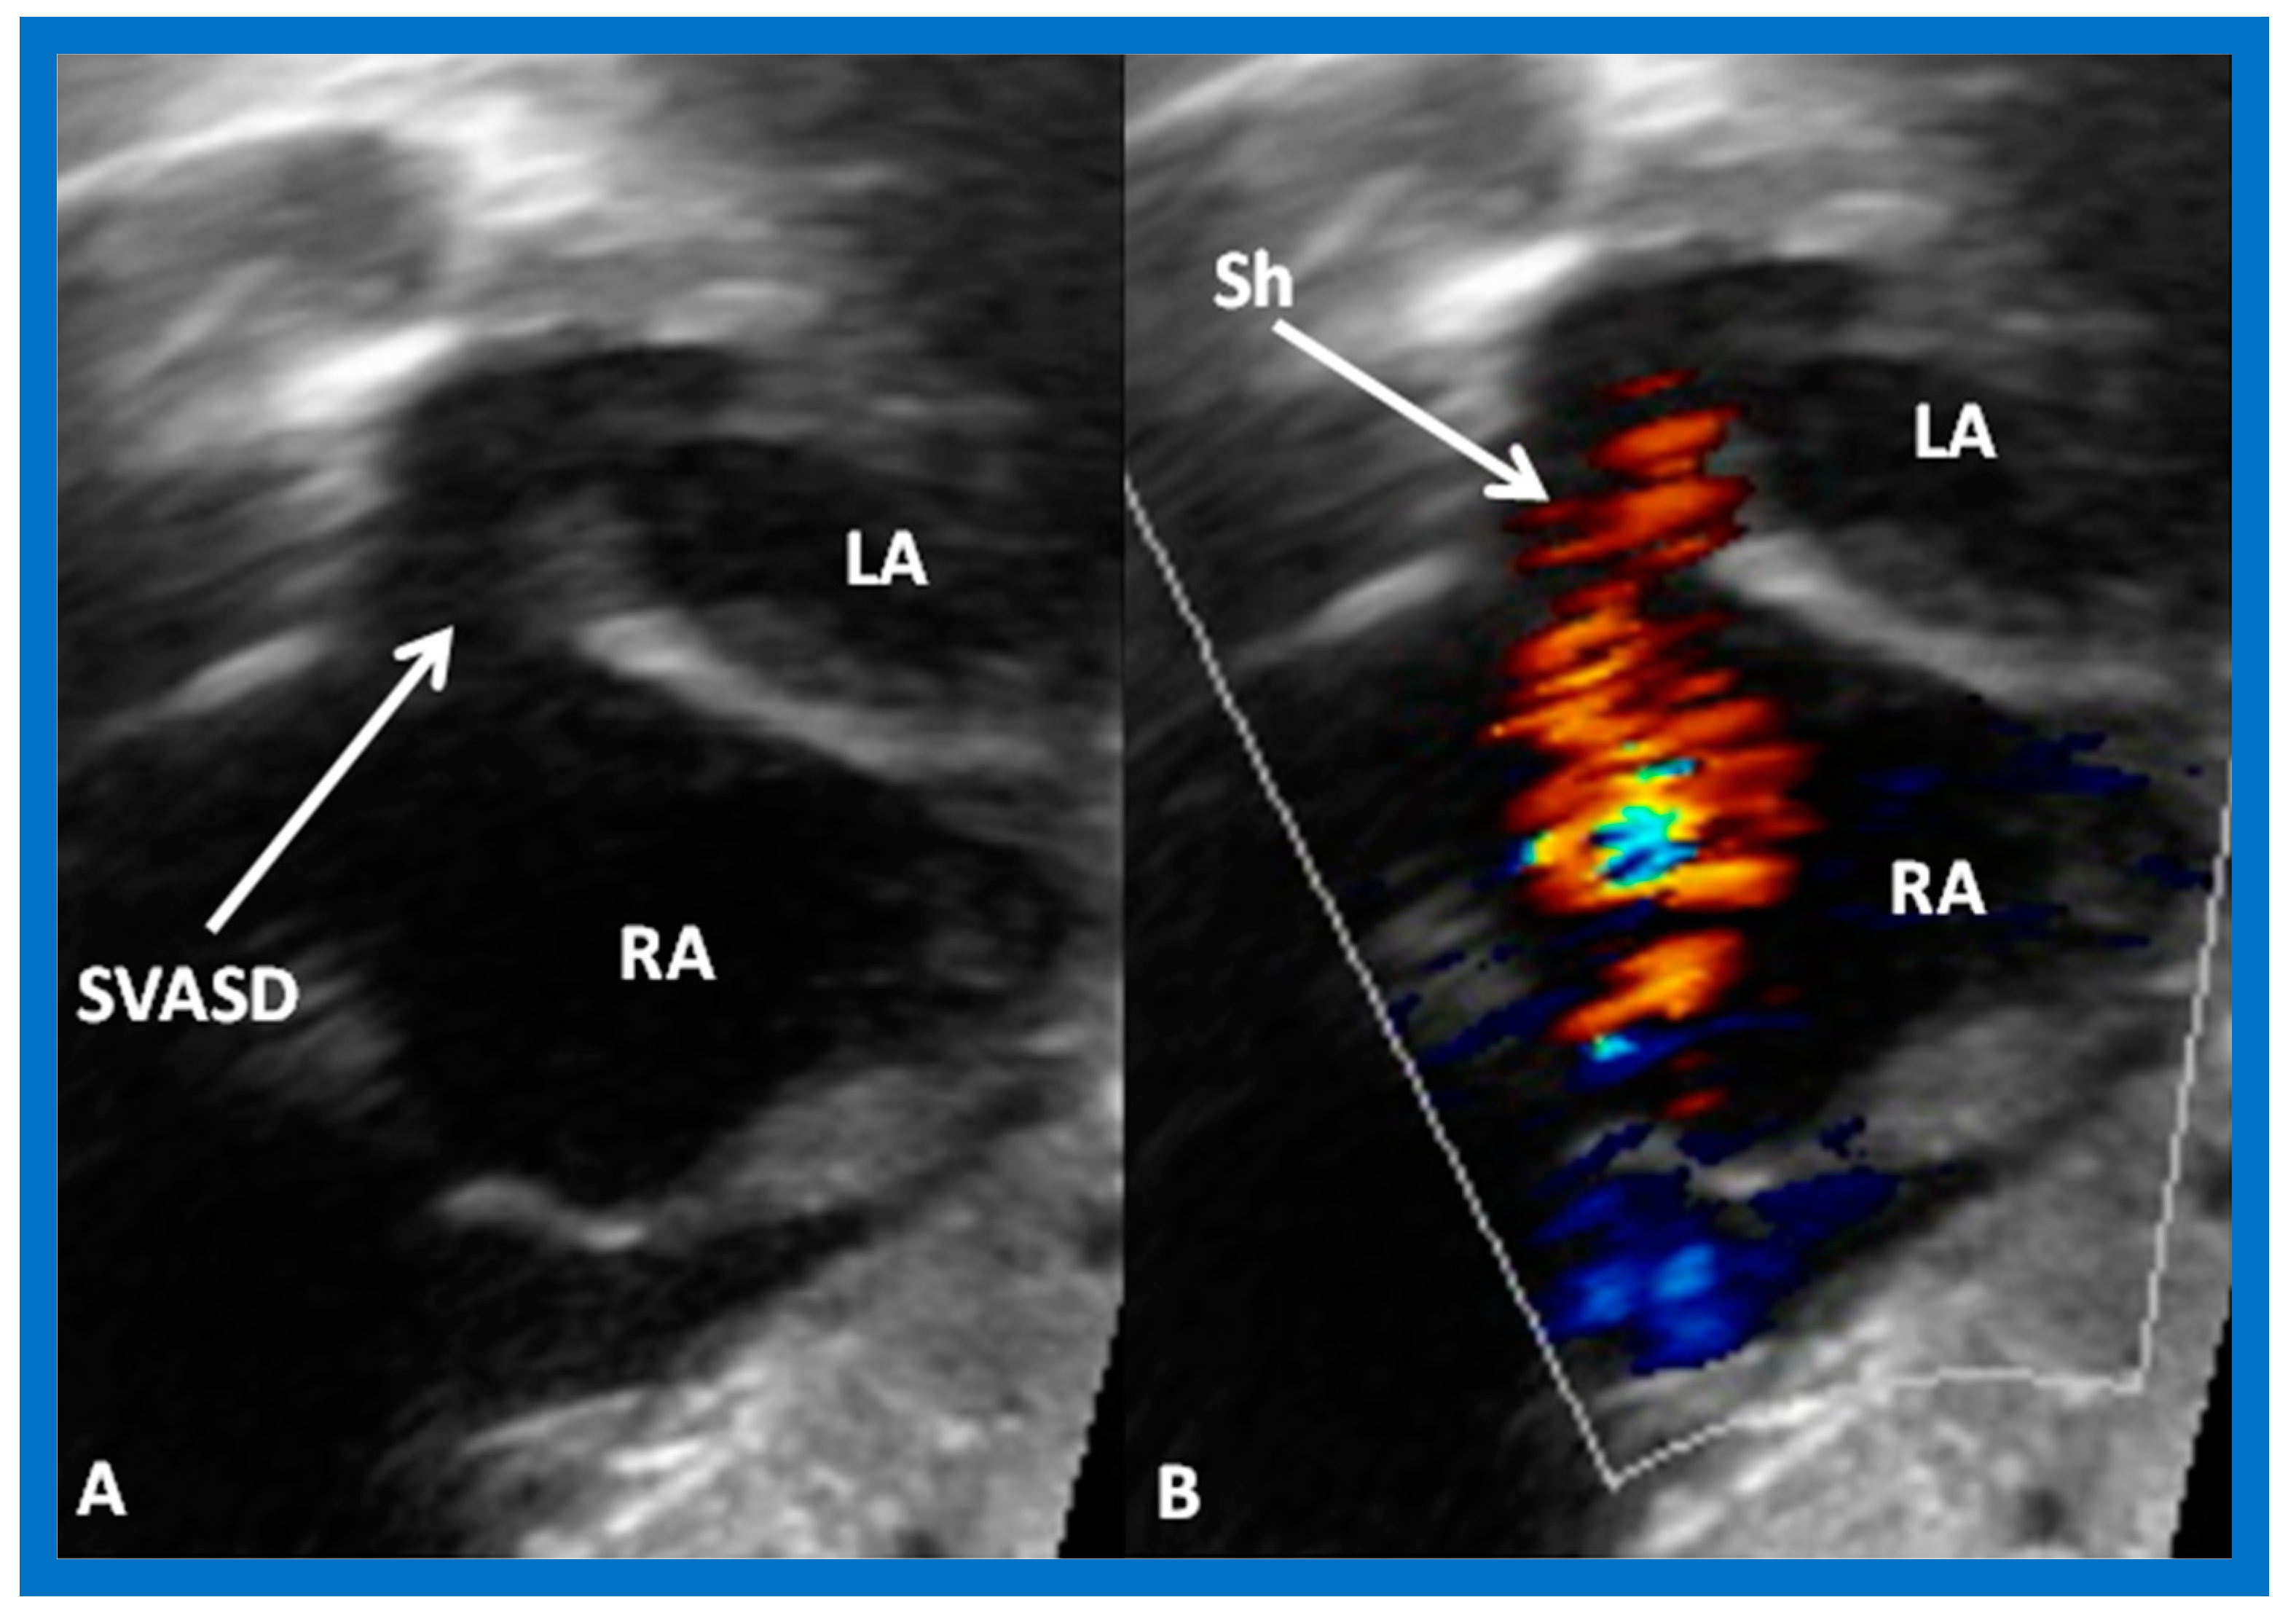

2. Diagnosis